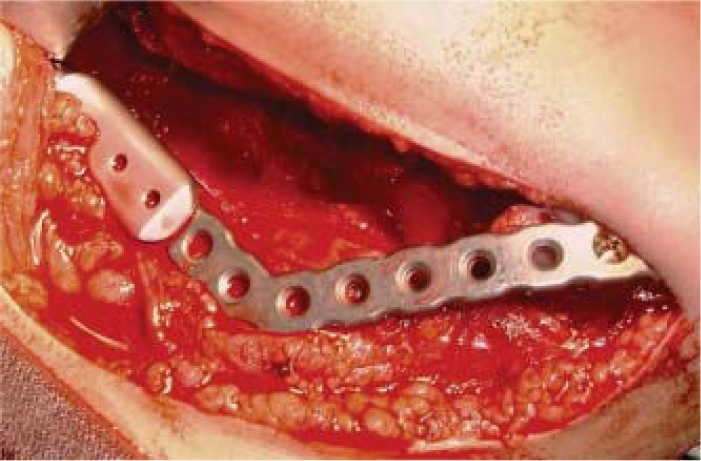

Eight year old female patient who attended the clinic with increase in left hemi-mandibular volume. Lesion was of a 5 month evolution with fast, painful growth (Figure 6). Intra-orally, expansion of vestibular cortical bone was observed, with tooth displacement (Figure 7). X-rays revealed a lesion destroying part of the body and ramus on the left side of the mandible, nevertheless, condyle and coronoid apophyses were preserved (Figure 8). The patient did not exhibit any other relevant data; laboratory exams yielded normal parameters. Result of incision biopsy was mandibular plexiform ameloblastoma. Block excision was undertaken in view of the lesion's local aggressive behavior (Figure 9). A reconstruction prosthesis was placed with preservation of condyle and coronoid apophyses (Figure 10). No complications were observed during post-operative period; motor and nerve structures were preserved. The patient exhibited suitable oral opening and appropriate facial appearance (Figure 11).